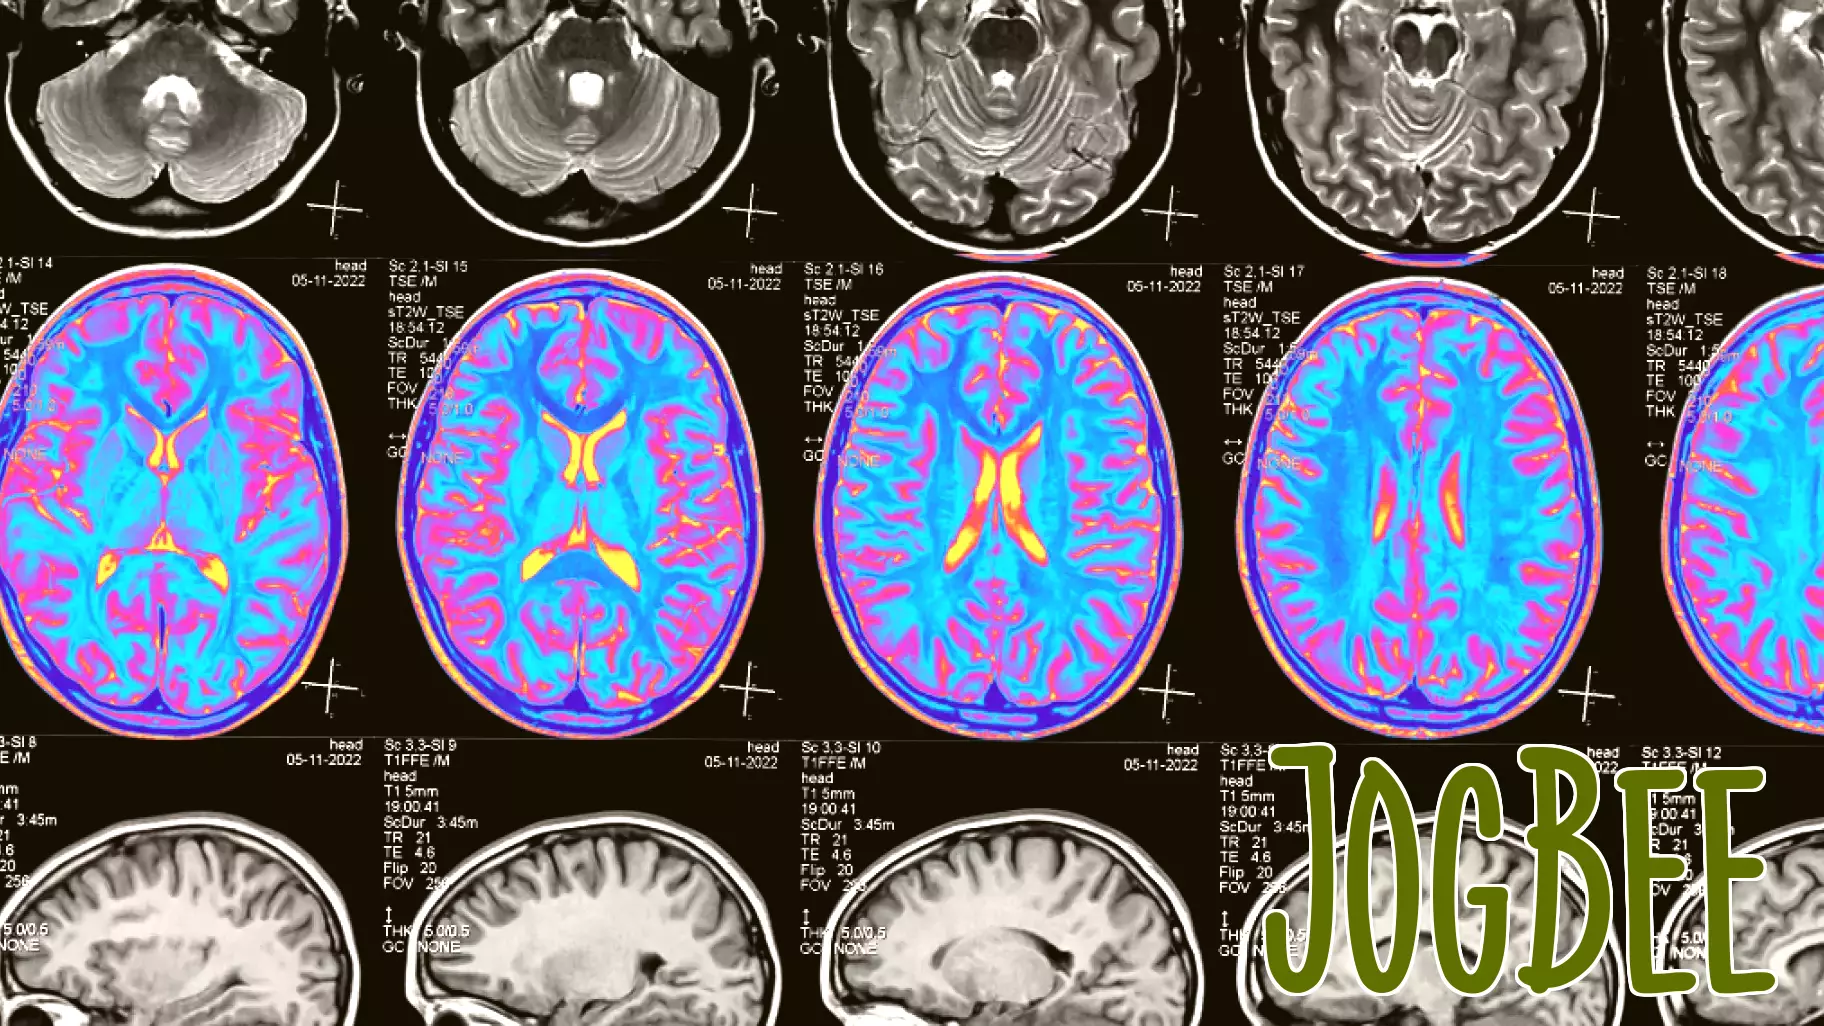

"My new memoir, Fit Into Me, delves into the intricate relationship between health, identity, and the often-overlooked topic of mild traumatic brain injuries. The narrative chronicles my journey from the conclusion of my MFA program to the present day, capturing the challenges and revelations that emerged during my recovery.

Through a series of poignant reflections, I explore how this invisible injury has reshaped my understanding of self and creativity. The memoir serves not only as a personal account but also as a broader commentary on the societal stigma surrounding brain injuries. It highlights the struggles that many face when grappling with the aftermath of trauma, often feeling isolated and misunderstood.

By sharing my story, I aim to foster a deeper conversation about mental health and the complexities of identity. It is a call to acknowledge the invisible wounds that affect countless individuals, encouraging empathy and understanding in a world that often overlooks such experiences."